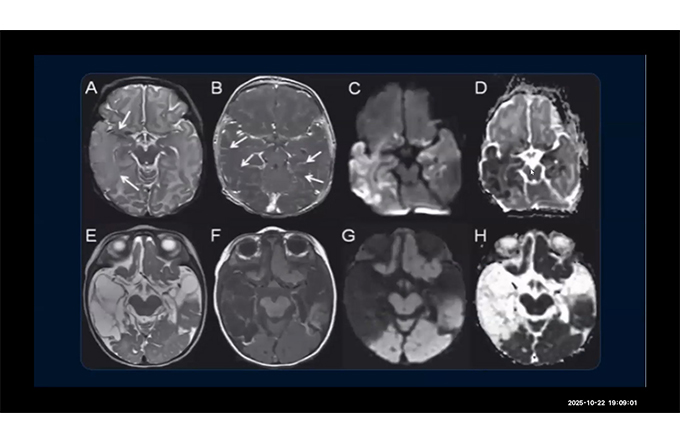

Neuro - Only Cases

RWRW Webinar

radiology